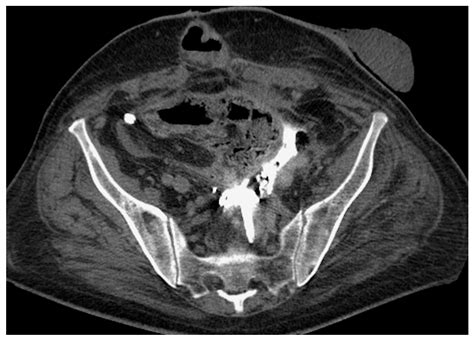

The stent is typically made of medical-grade plastic or silicone, designed to be biocompatible, meaning it can safely remain inside the body for a specific period. It features small curls at both ends—one sitting in the kidney and the other in the bladder—which act as anchors to keep the device from moving out of place. This design is why they are often called "double-J" or "pig-tail" stents.

4. Stent Placement: The stent is threaded over the guidewire and moved into the correct position. Once verified using X-ray imaging (fluoroscopy), the guidewire is removed, leaving the stent in place.